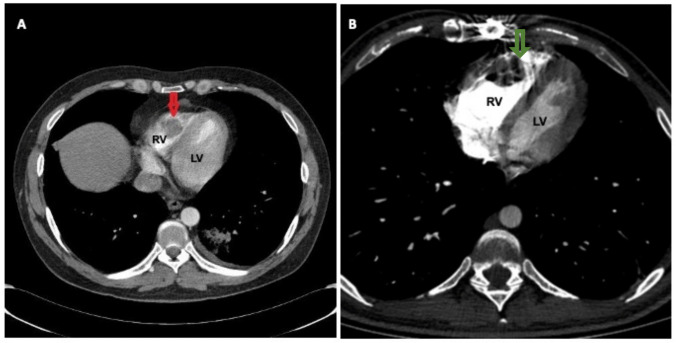

Purpose of the review: Behçet's Syndrome (BS) is a multisystemic vasculitis that can affect the heart, leading to pericarditis, myocarditis, intracardiac thrombosis, endomyocardial fibrosis, valvular dysfunction, and coronary artery disease. This review summarizes the clinical presentation, diagnostic challenges, and therapeutic strategies for cardiac involvement in BS.

Recent findings: Advanced imaging techniques have revealed subclinical cardiac involvement in BS. Myocardial dysfunction and fibrosis contribute to heart failure and arrhythmias, while intracardiac thrombi often coexist with pulmonary artery involvement. Coronary artery vasculitis and aneurysms may mimic atherosclerotic disease, complicating diagnosis. Biologic therapies, including TNF-α inhibitors, show promise in refractory cases. Early diagnosis and immunosuppressive therapy are crucial. A multidisciplinary approach is essential to managing cardiac complications and optimizing patient outcomes. Future research should refine screening protocols and explore targeted immunotherapies for BS-related cardiovascular disease.